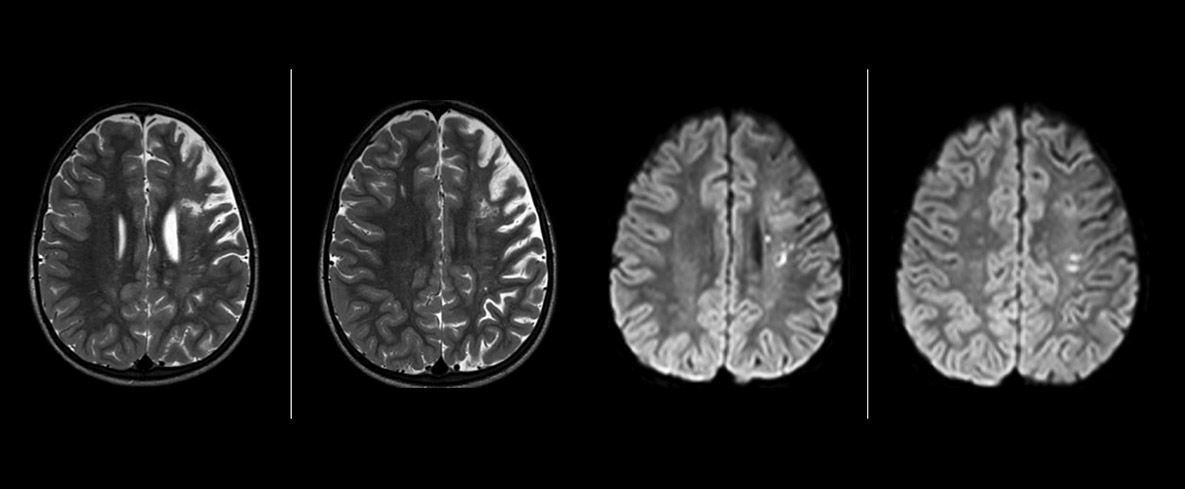

Pseudo-continuous arterial spin labeling (pCASL) was developed for brain perfusion imaging without contrast agent. “This is very desirable in pediatric patients where the general trend is to limit the administration of contrast,” says Dr. Miller. Growing confidence in specific applications “We built up confidence in pCASL by comparing it to contrast-based perfusion imaging. Once we had confidence that it was representing what the contrast perfusions were representing, we increased our diagnostic confidence by serial imaging in either the acute stage or the long term stages in a number of patients with arterial abnormalities.

Dr. Miller uses pCASL for all patients who present with chronic and acute cerebrovascular abnormalities such as acute stroke, as well as patients who present with signs of acute inflammation in the brain, and occasionally in patients with tumors, to assess the perfusion status of their tumor.

“In combination with diffusion weighted imaging, it can help give a more extended assessment of the degree of perfusion abnormality in a patient who is suffering acute ischemia. We have a number of patients who have chronic arterial insufficiency due to prior arterial abnormalities or acquired arterial abnormalities such as sickle cell disease or neurofibromatosis. Sometimes the child’s first manifestation of disease progression is a reduction in brain perfusion before stroke symptoms manifest clinically or in diffusion weighted imaging. We use pCASL to help delineate the perfusion abnormality.”

To other new users I would recommend to also start to interpret the pCASL images in comparison with other standard imaging – T2 and FLAIR and DWI – until the user gains confidence in interpreting these images by themselves.” “A powerful use of pCASL is in patients with chronic cerebrovascular stenosis, where clinicians desire information on how compensatory mechanisms of the brain are performing to enable perfusion to the brain. Often clinicians take into account how the compensatory mechanisms appear to help to provide adequate perfusion to the patient’s brain, and they may intervene surgically or make some other management decision.” “Another special application is the assessment of cerebrovascular reactivity with a Diamox perfusion exam, where we subtract two sets of pCASL images.”